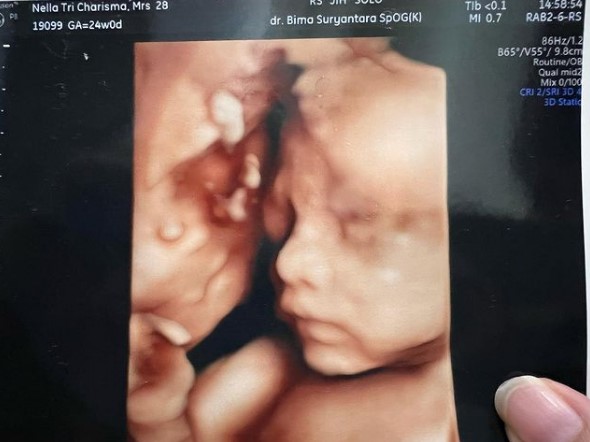

2. Nella mengunggah hasil USG 3 dimensi anak keduanya yang dinilai mirip dengan Dory Harsa. Nggak sedikit pula warganet menduga jika anak kedua Nella dan Dory itu berjenis kelamin laki-laki.